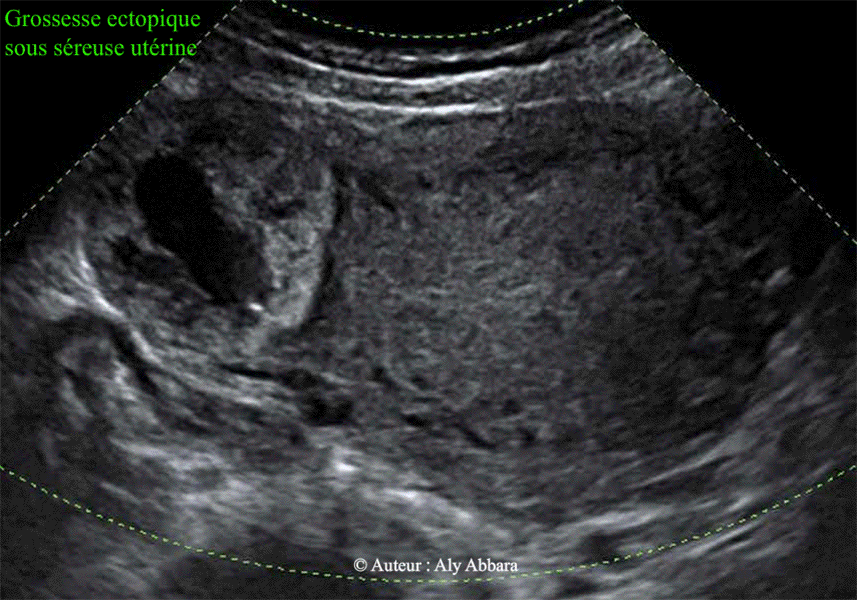

• Images échographiques par voie endovaginale montrant un sac gestationnel d'une grossesse débutante implantée à l'extérieur de la corne utérine droite du corps utérin, et à l'extérieur du myomètre (absence de couche myométriale autour du sac gestationnel permettant d’exclure le diagnostic de grossesse ectopique interstitielle ou cornuale).

• Ce sac gestationnel mesure 41,5 x 37,1 x 41,9 mm de diamètres (soit 33,8 cm3) ; il contient une vésicule ombilicale et un embryon de 8 mm sans activité cardiaque (donc grossesse arrêtée à 6+5 SA) ; le dosage de β-hCG plasmatique était égal à 65 500 UI/l.

A l'échographie : l'endomètre est 5 mm d'épaisseur ; absence d'épanchement péritonéal ; la présence du sac gestationnel décrit dans cette page, situé latéralement à droite, en contact direct avec la corne utérine et le tiers supérieur du bord latéral droit du corps utérin.

Le diagnostic de grossesse ectopique interstitielle (cornuale) n'a pas été retenu, parce que le sac gestationnel évolue, comme on peut le constater sur les images échographiques, à l'extérieur du myomètre ; il s'agit plutôt échographiquement d'une grossesse ectopique évoluant dans la portion isthmique de la trompe droite.